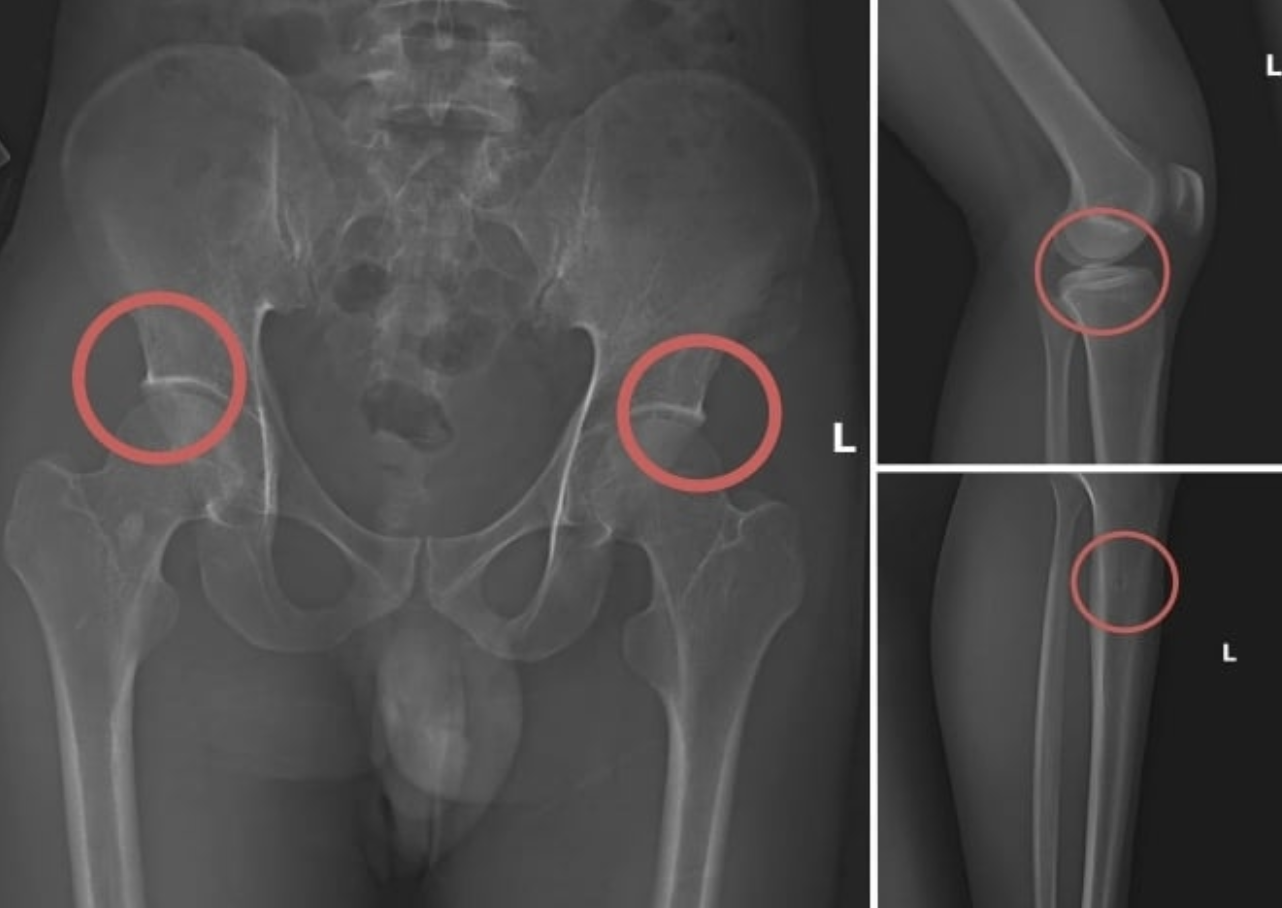

Old  Default Vụ tự đục gãy xương để chiếm đoạt hơn 6 tỷ đồng tiền bảo hiểm: Bác sĩ thốt lên "quá tàn nhẫn”

Liên quan tới vụ việc các đối tượng dùng kim tiêm, búa, đinh để tác động vào xương người mua bảo hiểm, tạo ra các vết nứt, gãy xương giả nhằm chiếm đoạt tiền từ các công ty bảo hiểm, bác sĩ Nguyễn Dương Nhật Thi, Bệnh viện Hữu nghị Việt Đức đã phải thốt lên: “Quá tàn nhẫn”.

Theo bác sĩ Thi, việc đục gãy xương để hưởng tiền bảo hiểm là hành vi cực kỳ nguy hiểm, coi thường sức khỏe và tính mạng con người. Việc làm này không chỉ gây đau đớn ngay lập tức, mà còn tiềm ẩn nhiều biến chứng nghiêm trọng.

Việc đục gãy xương có thể gây ra những biến chứng cấp tính như: sốc do mất máu, chịu đau đớn dữ dội, hoặc tắc mạch máu do mỡ từ tủy xương xâm nhập vào hệ tuần hoàn. Ngoài ra, gãy xương có thể làm đứt hoặc dập mạch máu, dây thần kinh, dẫn đến chảy máu, mất cảm giác, liệt chi...

Bác sĩ Thi phân tích các biến chứng muộn do đục gãy xương cũng không kém phần nguy hiểm. Xương có thể liền chậm hoặc không liền hoàn toàn, dẫn đến biến dạng chi, lệch trục xương, ngắn chi, hoặc teo cơ, xơ cứng khớp nếu chức năng vận động không được phục hồi đúng cách.

“Các hậu quả này ảnh hưởng trực tiếp đến khả năng vận động, chất lượng cuộc sống, thậm chí gây đau mạn tính, tác động lâu dài và tăng gánh nặng kinh tế cho người bệnh và gia đình”, bác sĩ Thi nhấn mạnh.

Ngoài ra, nạn nhân còn phải đối mặt với các rủi ro y tế từ phẫu thuật nhằm điều trị gãy xương nhân tạo như nhiễm trùng vết mổ, sưng phù, chảy máu hoặc tác dụng phụ của thuốc. Nếu điều trị không hợp lý, các tổn thương này có thể dẫn đến thoái hóa sớm các khớp, đau mạn tính dai dẳng, ảnh hưởng chất lượng sinh hoạt và kinh tế lâu dài.

Trước đó, vụ án được cơ quan điều tra phát hiện sau khi tiến hành thu thập tài liệu liên quan. Tạ Minh Châu (30 tuổi, cựu cán bộ Trung tâm Y tế huyện Cẩm Khê – Phú Thọ) được xác định là chủ mưu, kẻ cầm đầu. Châu lợi dụng kinh nghiệm lâu năm trong ngành y, am hiểu cấu tạo xương và cơ chế chi trả bảo hiểm đối với thương tích gãy xương nên đã dựng lên một quy trình trục lợi bảo hiểm bài bản.

Đường dây này được tổ chức từ việc vận động người dân mua bảo hiểm, gây thương tích nhân tạo, cho đến hợp thức hồ sơ bệnh án để chiếm đoạt tiền. Khi thương tích đã được tạo ra, Châu cùng đồng phạm dựng hiện trường giả, từ điện giật đến trượt chân ngã suối, nhằm hợp pháp hóa hồ sơ yêu cầu chi trả.